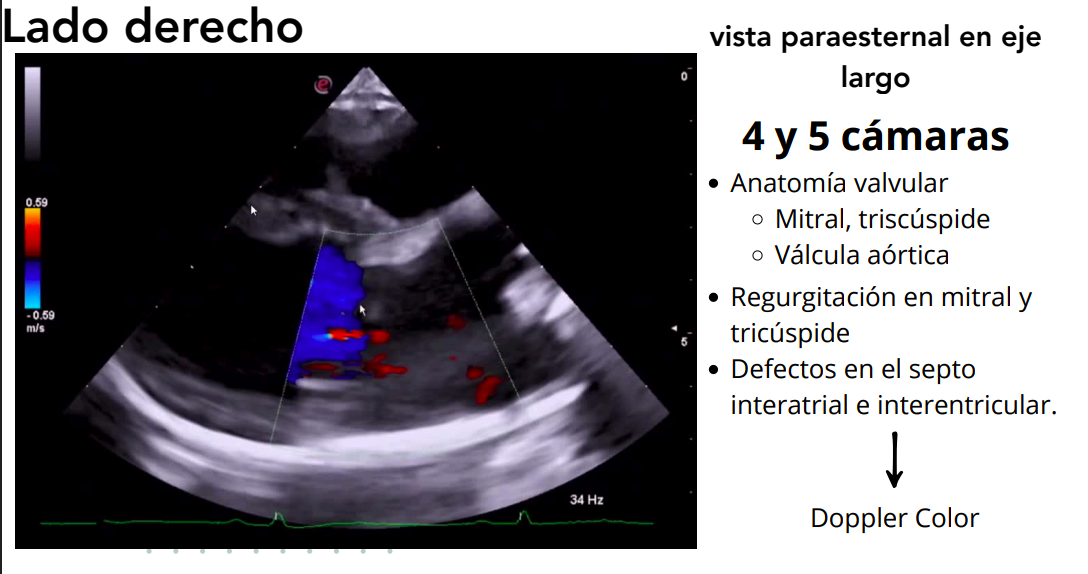

Vista paraesternal en eje largo

- 4 cámaras y 5 cámaras (incluye tracto de salida del VI).

- Evaluación de:

- Válvulas mitral, tricúspide y aórtica.

- Regurgitaciones valvulares.

- Defectos en septos interatrial e interventricular.

Doppler color: muestra regurgitaciones.

Doppler espectral: analiza velocidades de flujo.